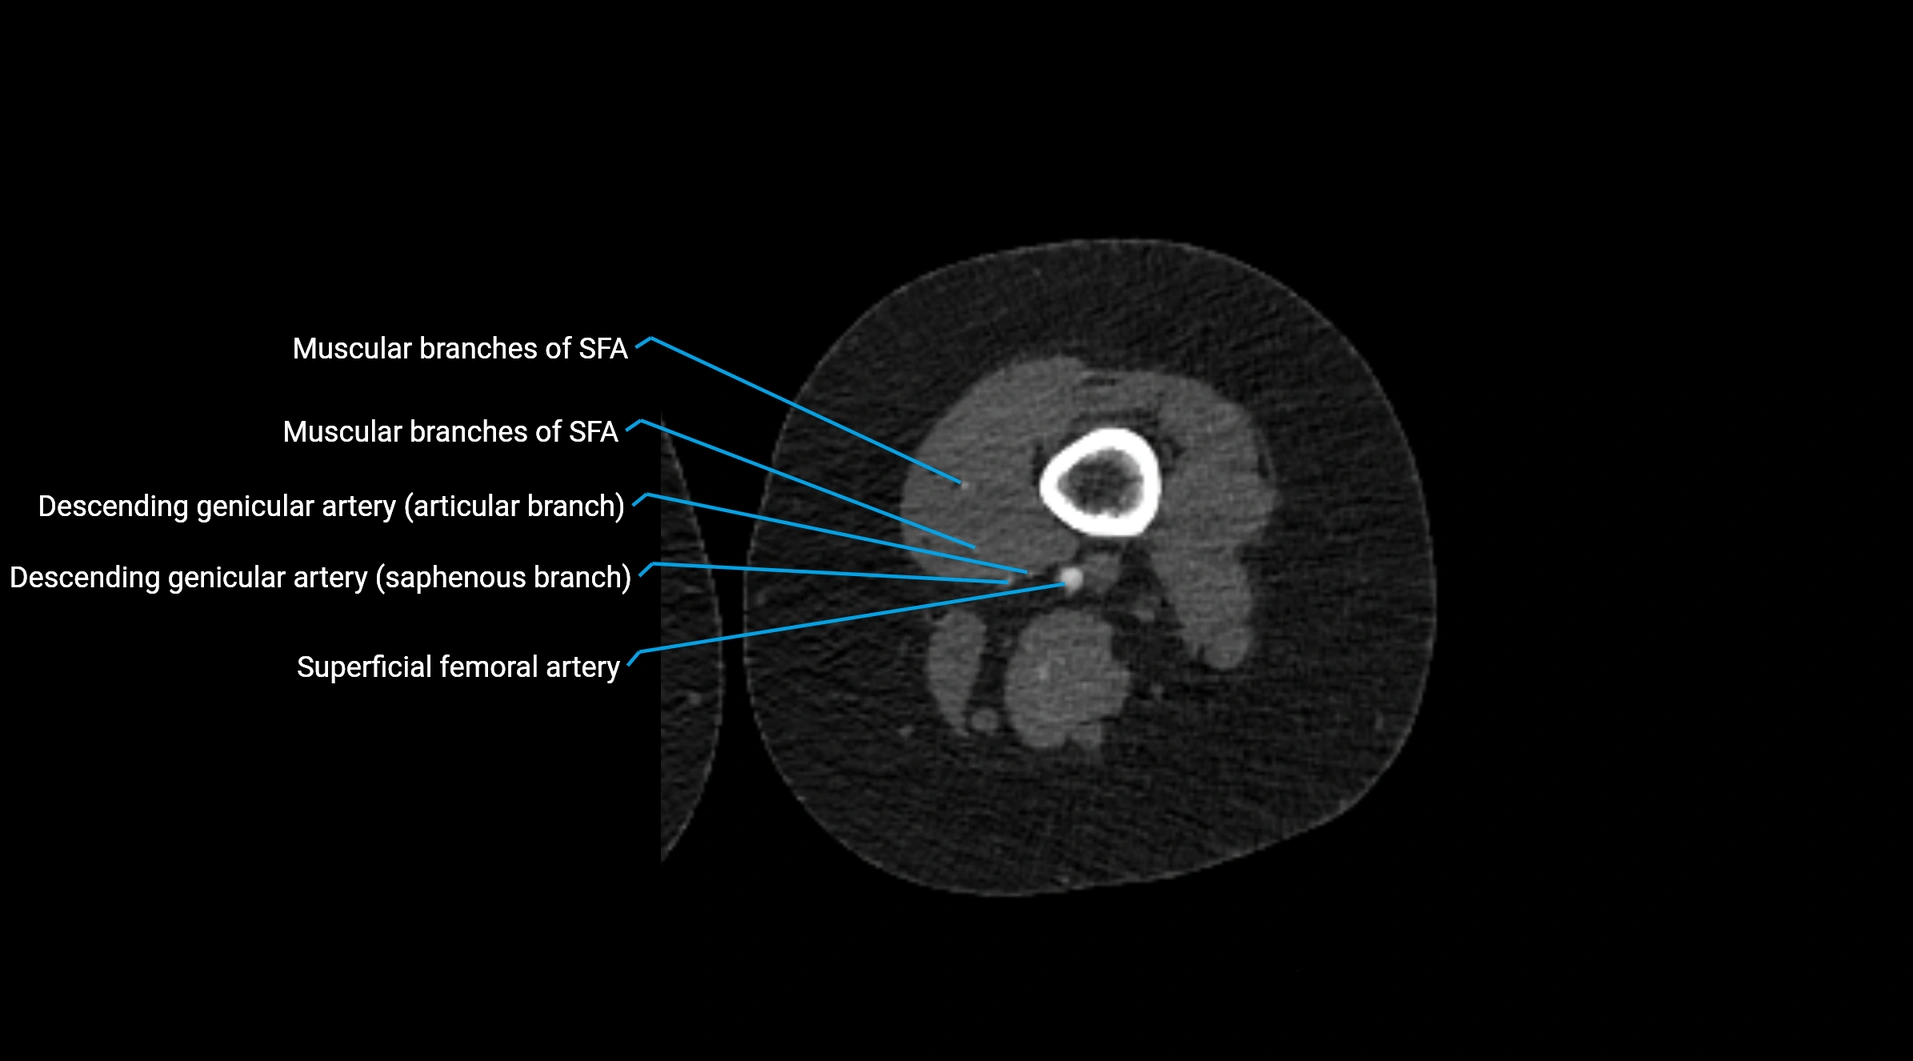

Contrast-enhanced CT (CTA):

• Gold standard for abdominal aortic imaging

• Provides excellent detail of lumen, wall, aneurysm, thrombus, and branch vessels

• Multiplanar and 3D reconstructions help in aneurysm measurement, stent graft planning, and dissection evaluation

• Detects acute rupture, traumatic injury, or occlusion with high sensitivity